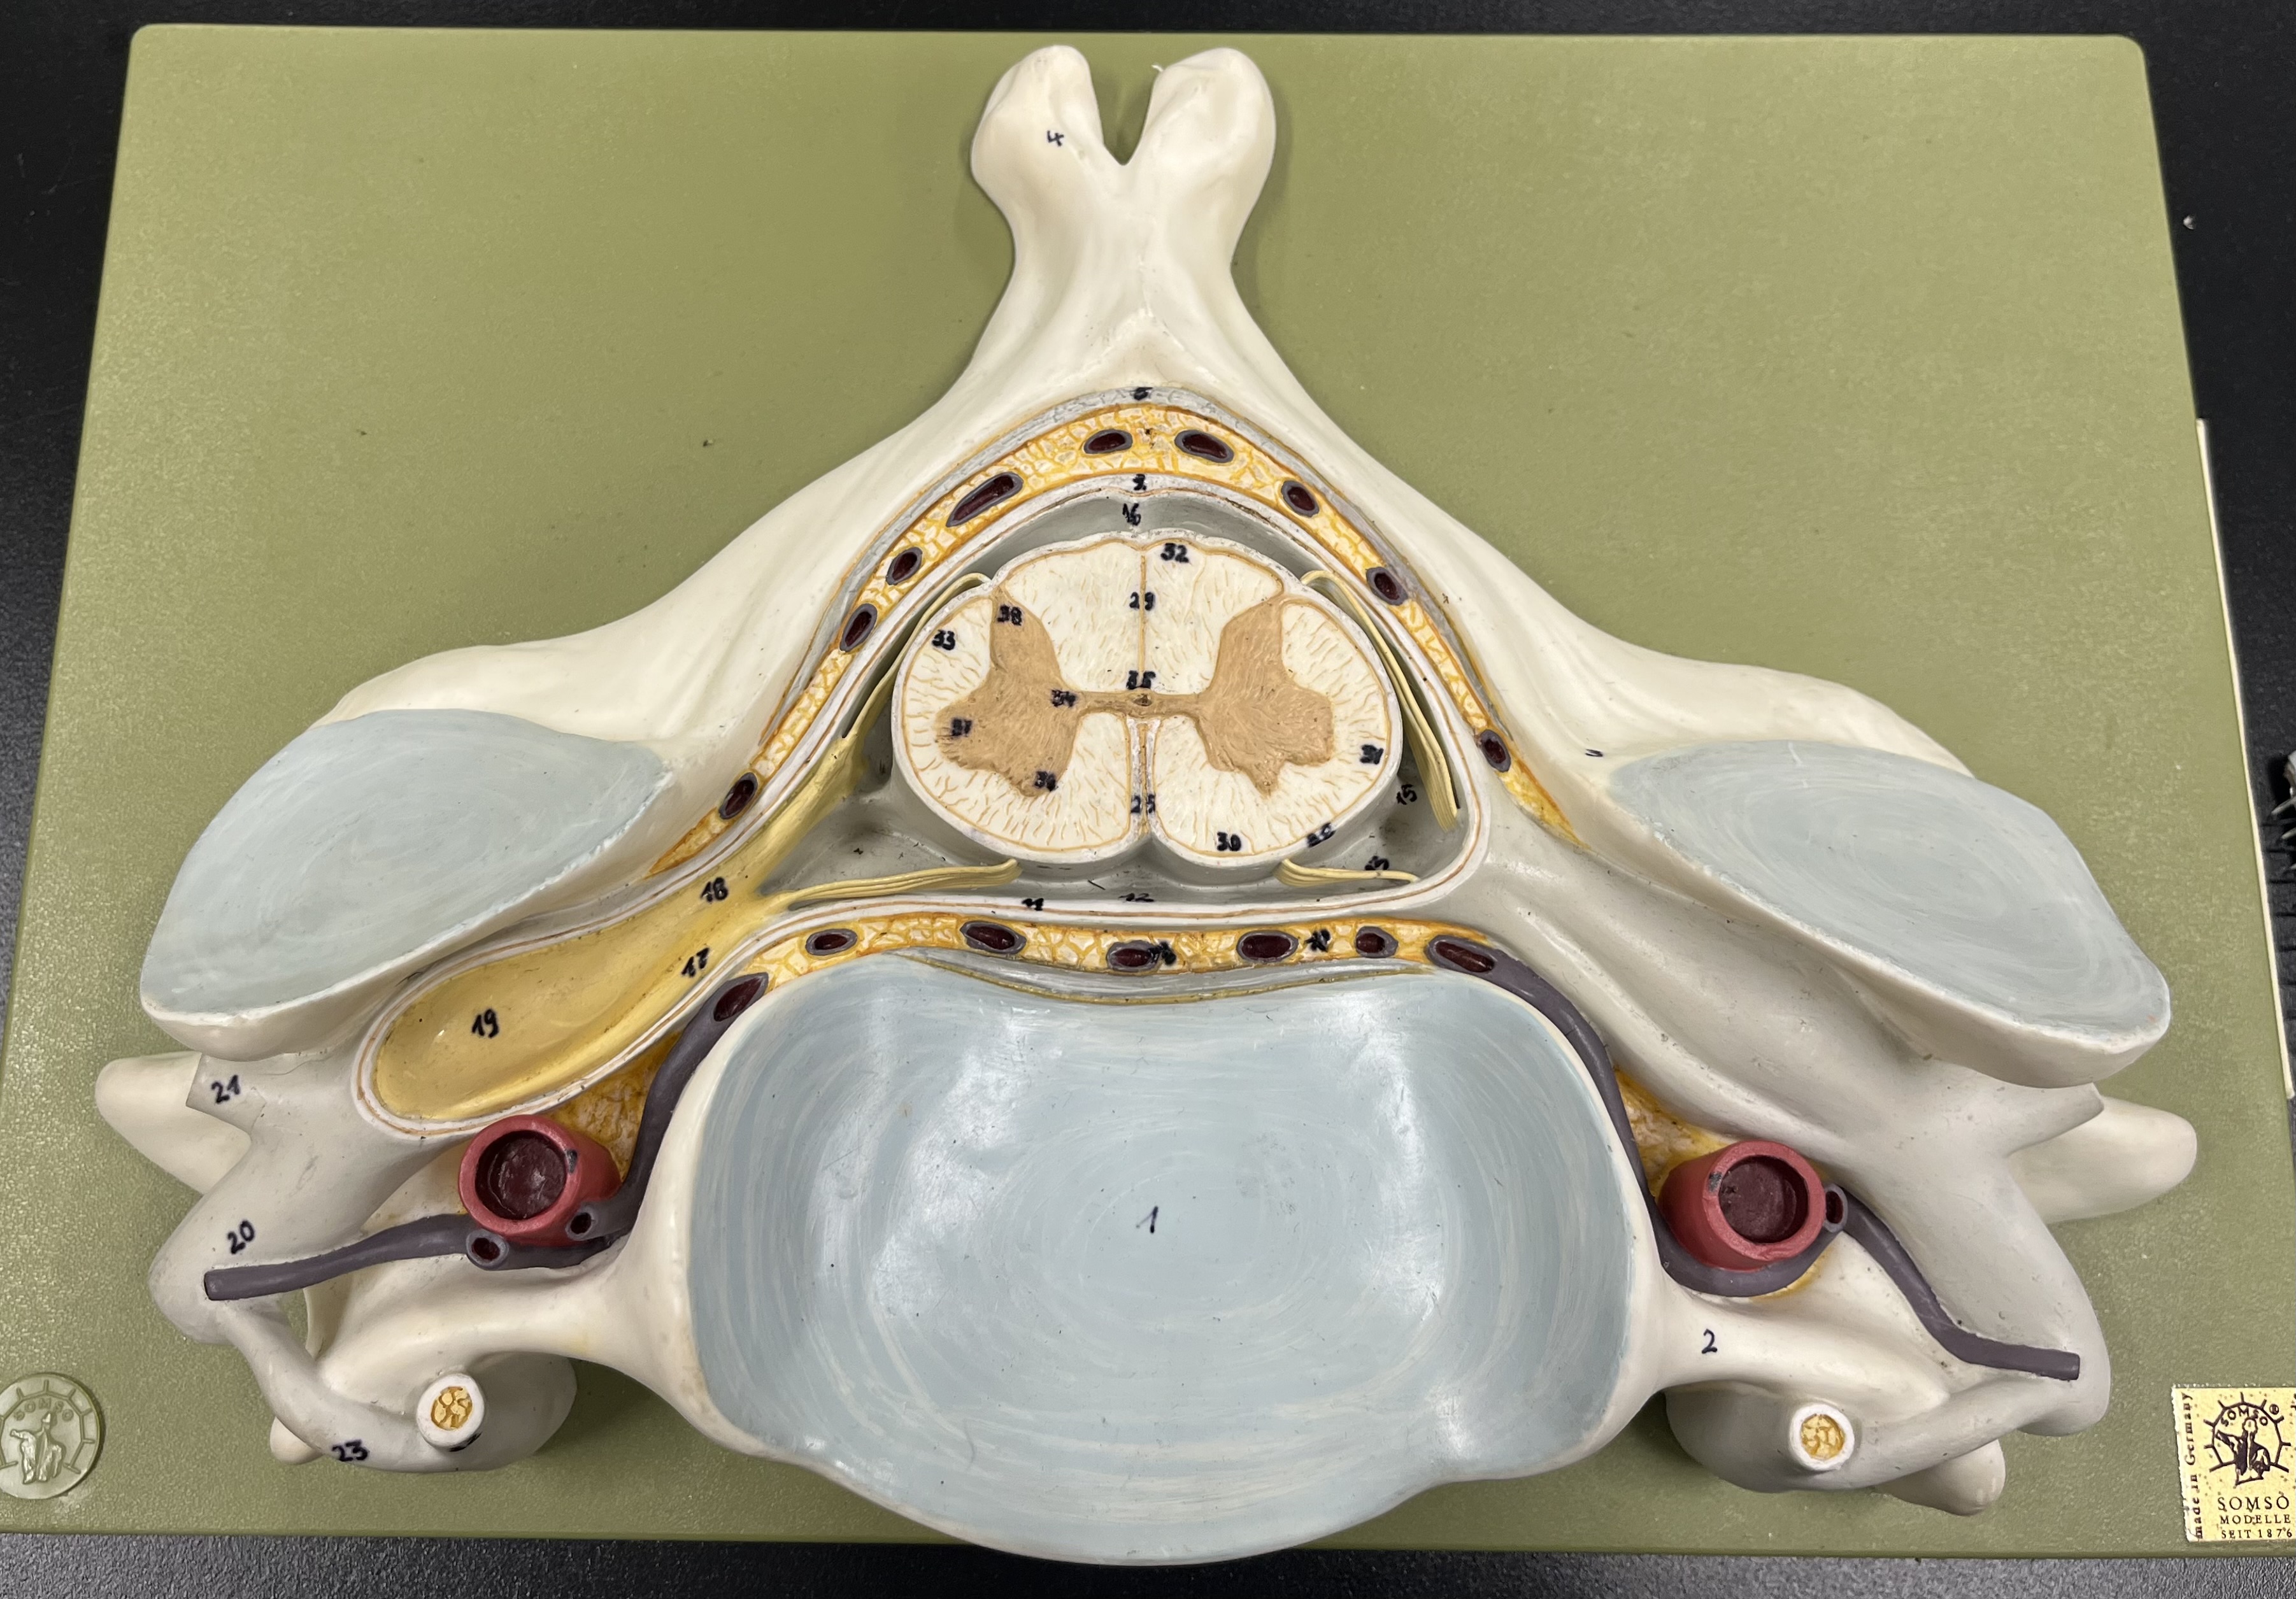

epidural space

dura mater

subdural space

arachnoid mater

subarachnoid space

pia mater

denticulate ligaments

What is the groove here?

anterior median fissure

posterior median sulcus

posterior (dorsal) horn

posterior (dorsal) horn; R—>L

anterior (ventral) horn

lateral horn (selected models)

gray commissure

central canal

anterior column

lateral column

posterior column

white commissure

posterior (dorsal) root ganglion

What is the bulb here?

posterior (dorsal) root ganglion

posterior (dorsal) root

posterior (dorsal) root

anterior (ventral) root

anterior (ventral) root

dorsal ramus

dorsal ramus

ventral ramus

ventral ramus

rami communicantes

rami communicantes

sympathetic chain ganglia

sympathetic chain ganglia